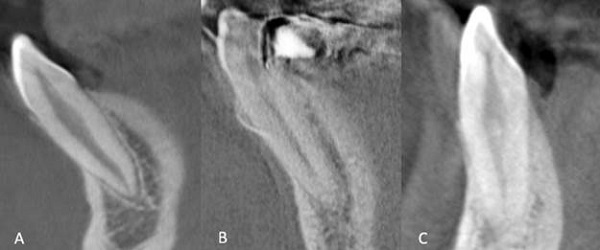

The most common root canal pattern in the mandibular canines had the same pattern, with a single root and a single canal. Type III was observed most frequently among teeth with two root canals, followed by Types II; Types IV, V, VI, VII, and VIII were not observed (Figure 2). The prevalence of an additional canal in the mandibular canine teeth in this study was 7,2%, which was close to the findings of Han et al. (6,3%) (2), Rahimi et al. (9,4%) (17), Kayaoğlu et al. (6,1%) (22), Altunsoy (female 6%, male 8,4%) (21), and Mağat (9,4%) (23), but lower than those of Amardeep (20,4%) (5), Vertucci (22%) (18), Çalışkan et al. (19,6%) (19) and Sert and Bayırlı (24%) (20), and Büyükbayram et al. (15,84%) (24) (Table 6).

In all other studies, Vertucci Type I has been observed as the most prevalent, as in our study. Of the double root canals, Types II and III were the most observed canal types in previous studies. In studies conducted with CBCT (2,5,18,19,20,21,22,23,24) the most common type of double root canal was Type III, as in our study.